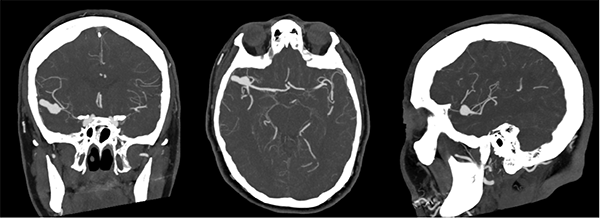

El laboratorio se encontraba dentro de parámetros normales, se realizó resonancia magnética (RM) de cerebro sin contraste, la cual mostró una imagen hipointensa en secuencia GRE a nivel del surco silviano derecho y adyacente a la misma se observa edema perilesional que se extiende al lóbulo temporal (Figura 1). Se realizó angiotomografìa para descartar una malformación vascular subyacente, en la cual se advirtió una dilatación aneurismática polilobulada de 20 x 6 x 9 milímetros (Figura 2).

Figura 1: A nivel del surco silvano derecho y en relación a la arteria cerebral media homolateral, se evidencian imágenes de baja señal en secuencia de gradiente eco (GRE) de aspecto sacular (A), en secuencia FLAIR se observa a nivel del surco Silviano en territorio de la arteria cerebral media derecha imagen hipointensa de forma sacular sugestiva de probable formación aneurismática, adyacente a la misma se aprecia hiperintensidad en parénquima cerebral sugestiva de edema (B y C).